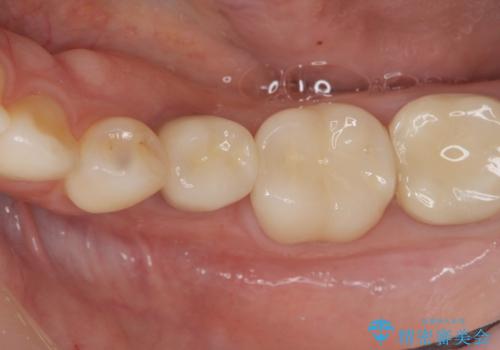

- 44万円(仮歯・ジルコニアクラウン・インプラント・アバットメント)費用は治療当時の料金となります

残念ながらぐらつきが大きくなり、残すことが難しくなり抜去したのちインプラントを用いて咬合機能の回復をしっかりと行いました。